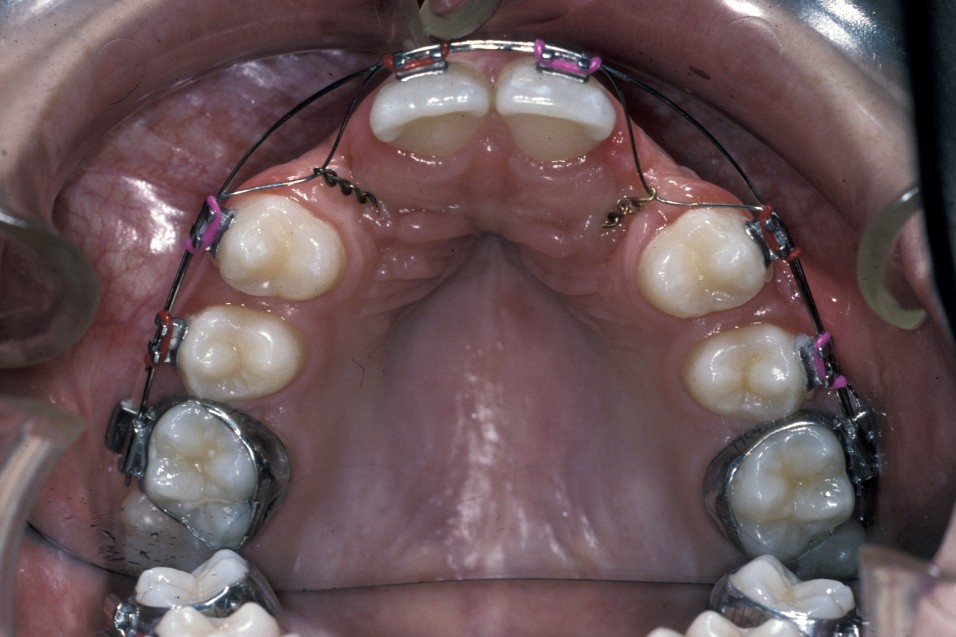

For satisfactory results to be achieved by surgical exposure and alignment of ectopic canines, complex fixed-appliances treatment for sometimes in excess of two years is required. Such appliances may include the need for dual-arch fixed appliances to allow for the use of interarch elastics and to allow arch co-ordination.

Before surgery is undertaken a decision has to be made between open or closed eruption. The aim of any exposure is to uncover enough of the crown either to place an attachment or prevent recovering of the crown during the healing phase. The most important principle of surgery is to ensure the tooth will erupt through keratinized mucosa. If this does not happen, which can occur with buccally placed canines, then the post-treatment periodontal condition will be compromised. This can obviously affect gingival aesthetics and health.

Closed eruption uses an attachment secured to the tooth to apply orthodontic traction and is useful in the treatment of markedly ectopic teeth where it would be difficult to undertake an adequate open exposure. It is often used when the canine is palatally positioned. It can be used for the treatment of buccal canines but the results can be disappointing if the attachment herniates through the thin buccal gingivae. To avoid this, the attachment should be placed either on the tip of the tooth or palatally. This is sometimes not possible because the crown position increases the risk of either excessive bone removal or iatrogenic damage to adjacent structures. It is, however, useful in the treatment of buccal canines if the crown overlies an adjacent tooth and it would be difficult to undertake an apically repositioned flap.

Surgery involves the same access as for the removal of the tooth, except that great care must be taken not to damage the cementum of the root surface as this can lead to ankylosis of the tooth and subsequent failure of eruption. An adequate amount of the crown should be exposed to allow attachment of the bracket and chain. Prior to bonding the bracket to the tooth, the area should be as uncontaminated as possible. Bleeding should be arrested as much as practicable with the use of local application of vasoconstrictors (as is added to some local anaesthetics) or the use of diathermy. Once the area is prepared, the tooth surface should be washed with saline or water and then prepared for bonding either with acid etch or with self-etch priming agents. The latter offer the advantage that they do not need to be rinsed off, need less time to prepare the tooth and are to some extent hydrophilic.

Once the tooth surface has been prepared the bracket can be secured either with chemical- or light-cured composite. The bracket should be tested to ensure that it is securely in place prior to wound closure. The chain or ligature can either exit through the wound margin on the alveolar ridge or through a stab incision elsewhere if it is felt that this would give a better vector of traction to align the tooth. With teeth that are significantly ectopic or are close to the roots of adjacent teeth, it is sometimes useful for the orthodontist to be present at the time of surgery. This allows an assessment of the relationship of the canine to adjacent structures and to plan the vector of traction that will be most appropriate.

Open eruption is often the treatment of choice for both buccally and palatally ectopic teeth.